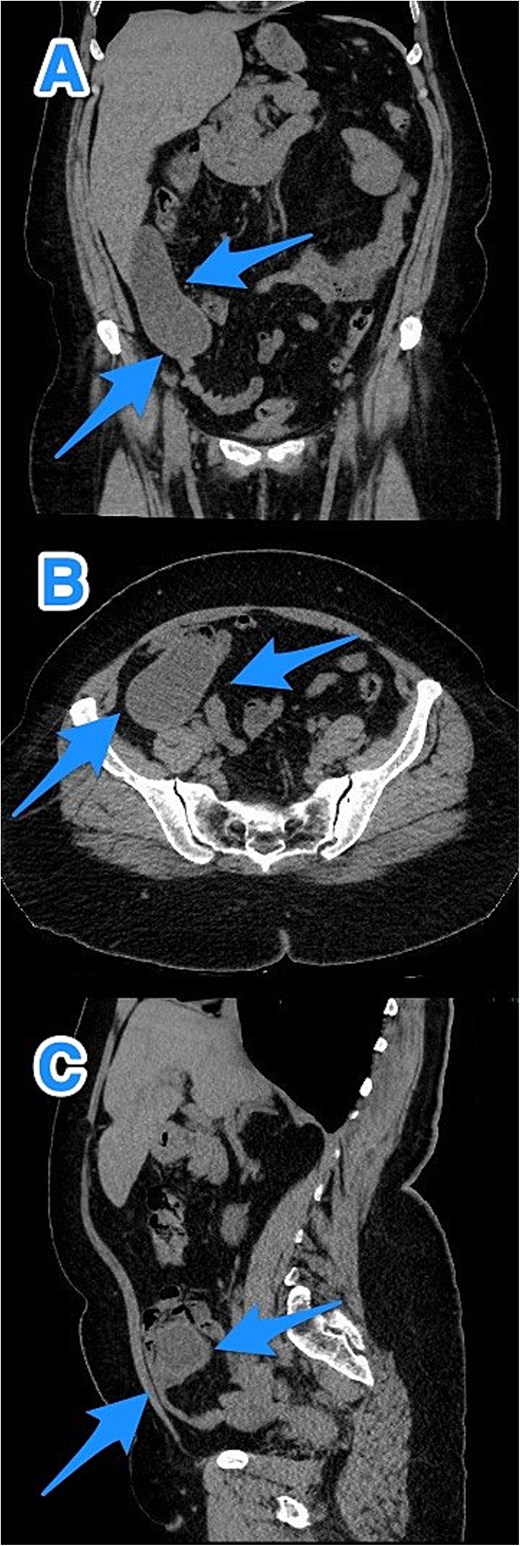

A 46-year-old male, with no previous medical or surgical history, presented to the emergency department with a 4-day history of right lower abdominal pain, which initially originated in the epigastric region before migrating to the right iliac fossa. It was constant, progressive, and not relieved by simple analgesics. The patient reported associated nausea and anorexia but denied any history of fever or vomiting. On physical examination, the patient was vitally stable, alert, conscious, and in moderate pain. There was rebound tenderness in the RLQ, and the remainder of abdomen was soft, with no other positive findings. Laboratory investigations were within normal ranges. Contrast-enhanced CT imaging of the abdomen and pelvis detected a dilated, blind-ended tubular structure in the right lower quadrant, with thick fluid content and incomplete calcifications along its circumference. A focal area of wall discontinuity with thick fluid collection in the right paracolic gutter and pelvis was observed (Fig. 3). Additionally, small ascites with thickened and enhancing peritoneal reflections were noted. The diagnosis of a ruptured appendiceal mucocele was made. A right hemicolectomy was performed, and the patient's postoperative course remained stable and uneventful.

CT abdomen and pelvis with contrast: (A) coronal, (B) axial, and (C) sagittal views demonstrate a dilated, blind-ended structure in the right lower quadrant with incomplete circumferential calcifications and thick fluid content, consistent with an appendiceal mucocele (arrows).

Pathological examination confirmed the diagnosis of LAMN (Fig. 4). Key findings included tumor disruption of the appendiceal wall, pushing invasion into the muscularis propria, and associated perforation. There was mucin dissection extending into the extra-appendiceal region, accompanied by a serosal reaction characterized by granulation tissue and acute inflammation. Both resection margins were tumor-free, and all 15 lymph nodes examined were negative for tumor infiltration. A focus of lymphovascular invasion was identified. Biopsies of the peritoneum and omentum demonstrated mucin dissection, extensive acute serositis, and inflammation. A referral to a higher center was initiated for comprehensive assessment and ongoing medical management.